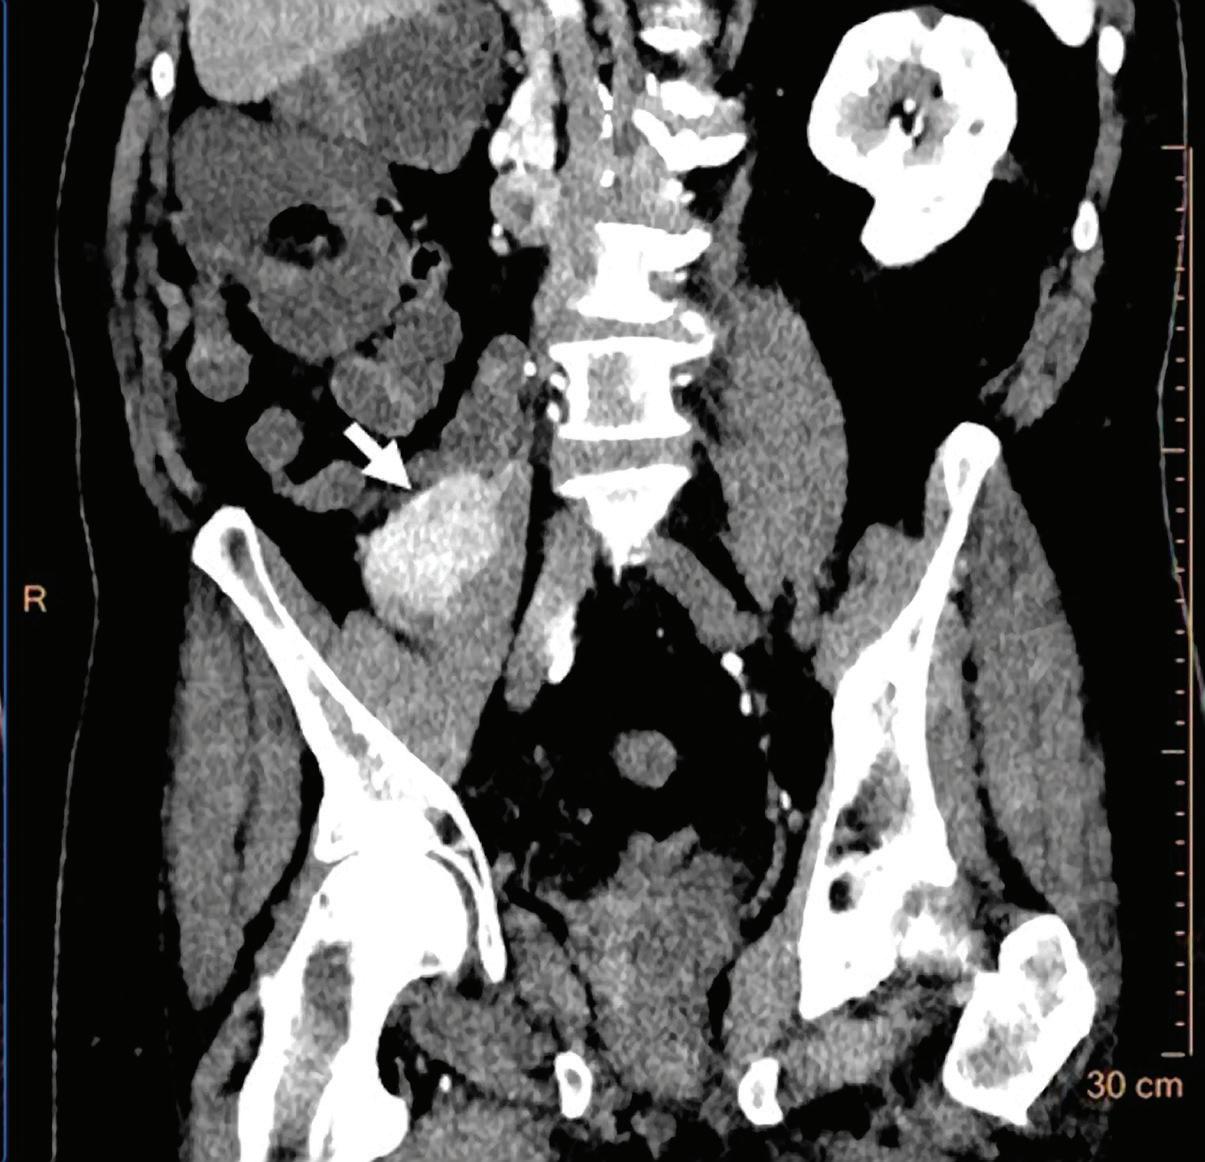

Patient presented to the emergency department with abdominal pain. The conventional CT does not reveal any abnormality in the gallbladder. In the middle row, spectral attenuation curves reveal two different materials: a first region of interest (purple) with a CT number that is increasing with energy, typical of a low Z effective element (below the Z effective value of water), and a second region of interest (blue) with a CT number that is decreasing with the energy, typical of a Z effective above water. The differentiation between the two materials cannot be performed based on the conventional CT because the two attenuation curves cross each other around 70 keV (where the attenuation is equivalent to the conventional CT). The lower row displays spectral results in the Magic Glass, from left to right: 40 keV image, 200 keV image, iodine density image, and Z effective map. A gallstone is clearly revealed on the 40 keV image and with an inverted contrast on the 200 keV image. The iodine density shows a perfusion defect of the gallbladder wall due to the compression with the gallstone (white arrow), and the Z effective helps us to determine the gallstone composition with a Z effective below 6.5 typical of a cholesterolic composition.